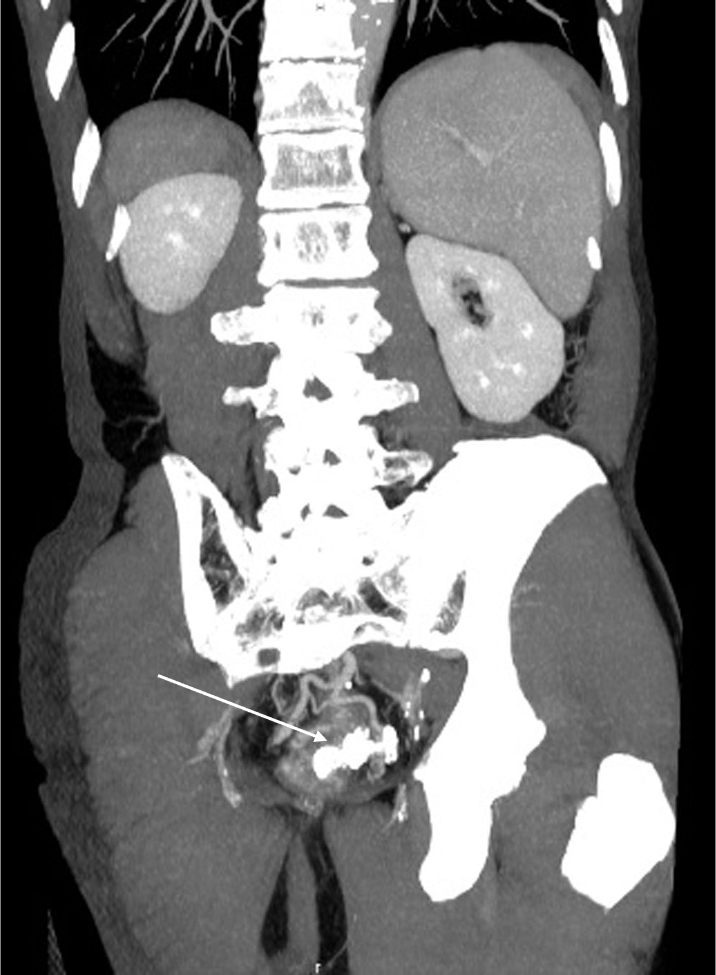

直腸静脈瘤の破裂予防目的にヒストアクリルを用いた経皮経肝的静脈瘤塞栓術を施行した。治療一か月後の治療効果判定に撮影を行った。

肝硬変のスクリーニング目的の造影CTにて直腸静脈瘤が判明した。破裂予防目的に経皮経肝的静脈瘤塞栓術を施行した。術前CTにて血管解剖を把握の上、治療を行った。術後一か月の造影CTにて、標的血管の良好な閉塞が確認された。

当該疾患の診断における造影CTの役割

直腸静脈瘤を始めとする異所性静脈瘤においては、IVR治療が選択されることが多い。術前に正確な解剖の把握が必要であり、造影CTの果たす役割は大きい。特に門脈系の良好な描出が求められ、適切な時相での撮影が肝要である。撮影後thin slice軸位断像での観察、任意多断面再構成像(MPR)やVolume rendering画像(VR)で評価を行い、術中のガイドとする。また肝細胞癌を併発することが多い為、動脈優位相における撮影も行う必要があり、dynamic studyを要する。治療においてはヒストアクリルや金属コイルなどのアーチファクト源となり得るデバイスが使用されるため、必要に応じてmetal artifact除去を活用する必要がある。また別部位に新たな静脈瘤が生じたり、腹水などの門脈圧上昇に伴う所見や門脈血栓などの合併症が生じる危険性があるため、造影CTによる評価が重要である。